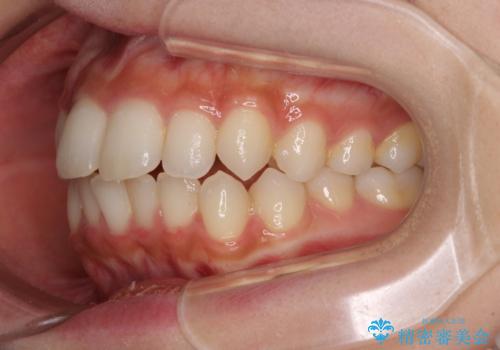

- 上下前歯のデコボコを気にして来院された患者様です。

前歯のセラミックが装着されている歯は、歯根が短くなっており、他院では抜けてしまうので矯正はできないと言われていたようです。

患者様と相談し、抜けてしまった場合にはインプラントあるいはブリッジによる補綴治療が必要となることを確認し、極力歯根に負担のかからないような仕上がりで治療を進めて行くこととしました。

デコボコを解消には、IPR(歯と歯の間を削る)をメインに歯列排列を設計し、インビザラインにて矯正治療を行うこととしました。

レントゲン写真上では、矯正治療前後で歯根長さに大きな違いはなく、抜歯を回避することができました。

上顎内側に転位している前から2番目の歯は移動が難しく、無理矢理歯根全体を動かそうと設計すると、歯肉退縮・歯髄壊死・歯根吸収といった危険性が増すため、無難なゴールにて治療を終えることとなりました。